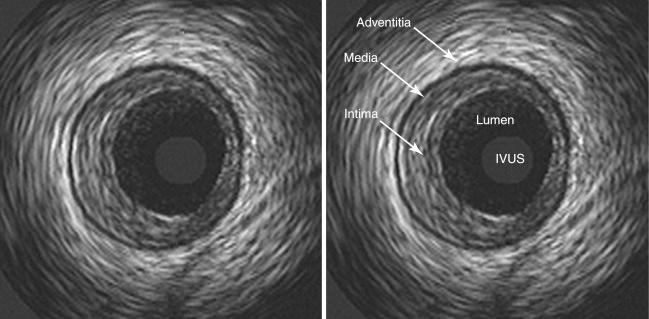

Intravascular Ultrasound (IVUS) is a catheter-based imaging technique used to visualise the inside of blood vessels, especially coronary arteries.